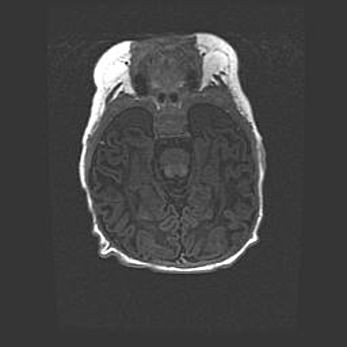

Неполная лизэнцефалия (пахигирия). Открытая гидроцефалия.

Возраст: 17 дней

Вес: 3110 г

Пол: мужской

Окружность головы: 33,5 см

Срок гестации: 35-36 недель

Лизэнцефалия—недоразвитие корковой пластинки и мозговых извилин в результате нарушения миграции нейронов коры. Поверхность мозговых полушарий гладкая. Микроскопически выявляется отсутствие нормальных слоев коры и скопление групп нейронов в подкорковом белом веществе.

Пахигирия—уменьшение числа вторичных извилин. В пораженном полушарии нервные клетки образуют толстый недифференцированный слой с неправильно расположенными нервными волокнами и группами гетеротопных клеток. Нервные клетки незрелые. Белое вещество истончено. При этом нередко аномально развит корково-спинномозговой путь.